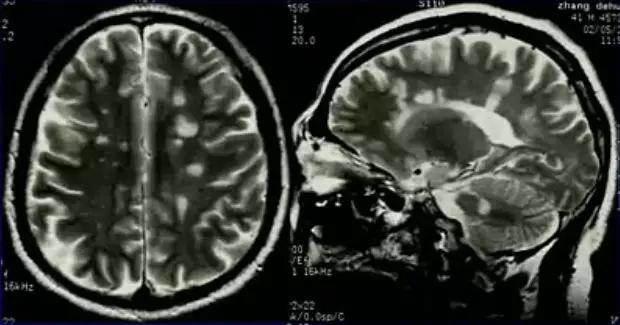

病理上桥脑中央髓鞘溶解症表现为桥脑基底部中央对称性脱髓鞘,从中缝向两侧发展,髓鞘脱失严重,神经细胞与轴突相对完整无炎性反应。桥脑周围部分不受累是本病特征。

T1 呈低信号,T2 呈高信号,病灶仅累及桥脑中央区,而边缘部分不受累,病灶前方和侧方仅存一薄层脑组织未受累,病灶后缘可延伸到被盖的腹侧。增强后一般无强化,但也可出现强化。

MRI 病变横切位上形态为原形或蝴蝶形,矢状位呈卵圆形,冠状位上呈蝙蝠翼状。